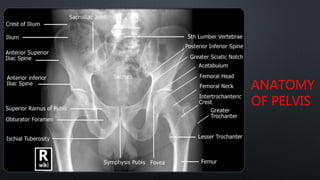

ANATOMY

OF PELVIS